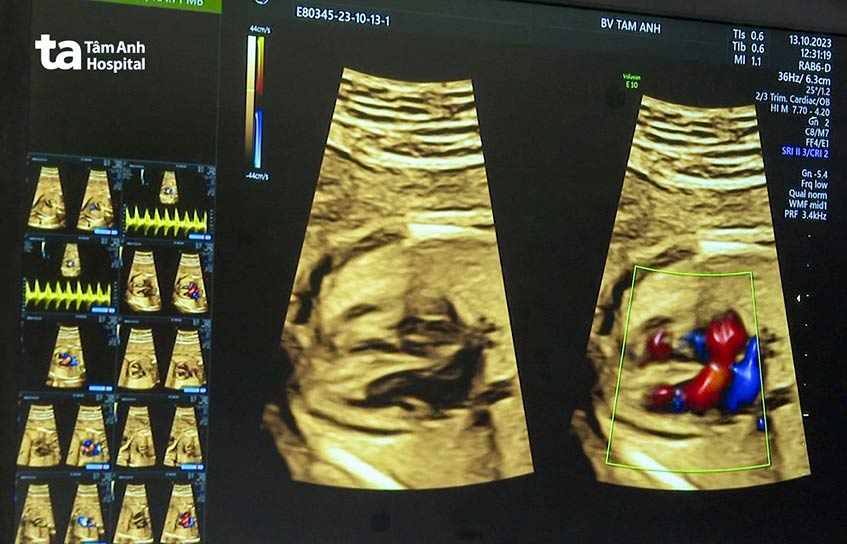

Từ cách siêu âm tim thai, tương quan hình thái/siêu âm tim thai, bệnh cơ tim thai nhi… được thực hiện trên máy siêu âm thế hệ mới chuyên dụng cho tầm soát bệnh lý tim bẩm sinh từ bào thai GE Voluson S8 Touch với phần mềm bản quyền ứng dụng trí tuệ nhân tạo. Nhờ hiệu ứng 3D của Doppler tự động phân tách từng mạch máu trong những tổ hợp mạch máu phức tạp, bác sĩ nhanh chóng phát hiện các bất thường về mạch máu như thông liên thất, hồi lưu tĩnh mạch phổi, chuyển vị đại động mạch, hẹp động mạch phổi… trên những quả tim nhỏ như đồng xu.

Bệnh viện Tâm Anh sử dụng máy siêu âm hiện đại có siêu “thuật toán” AI giúp bác sĩ siêu âm cắt, dựng hình, đo đạc cấu trúc tim từ bào thai nhỏ như đồng xu trong không gian 4 chiều, rút ngắn 70% thời gian chẩn đoán với độ chính xác cao vượt trội.